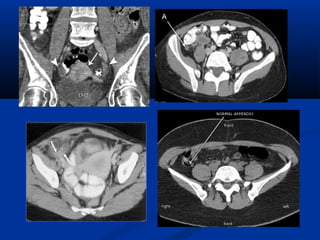

U maùu vuønghaømU maùu vuøng haøm (T)/(T)/ Daõn tónh maïchDaõn tónh maïch caûnh ngoaøi (T)caûnh ngoaøi (T)

Xaùc ñònh vò tríxöông söôøn treân CT

NOÄI SOI AÛOPHEÁ QUAÛN